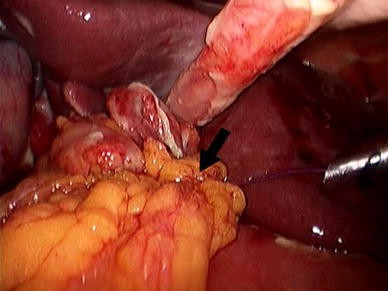

#Simple suture with omental patch Patch

The surgical treatment with a simple omental patch closure of the perforation has not changed much over a century and PPU still remains a life-threatening condition with a high mortality of up to 40% being reported ( 8).